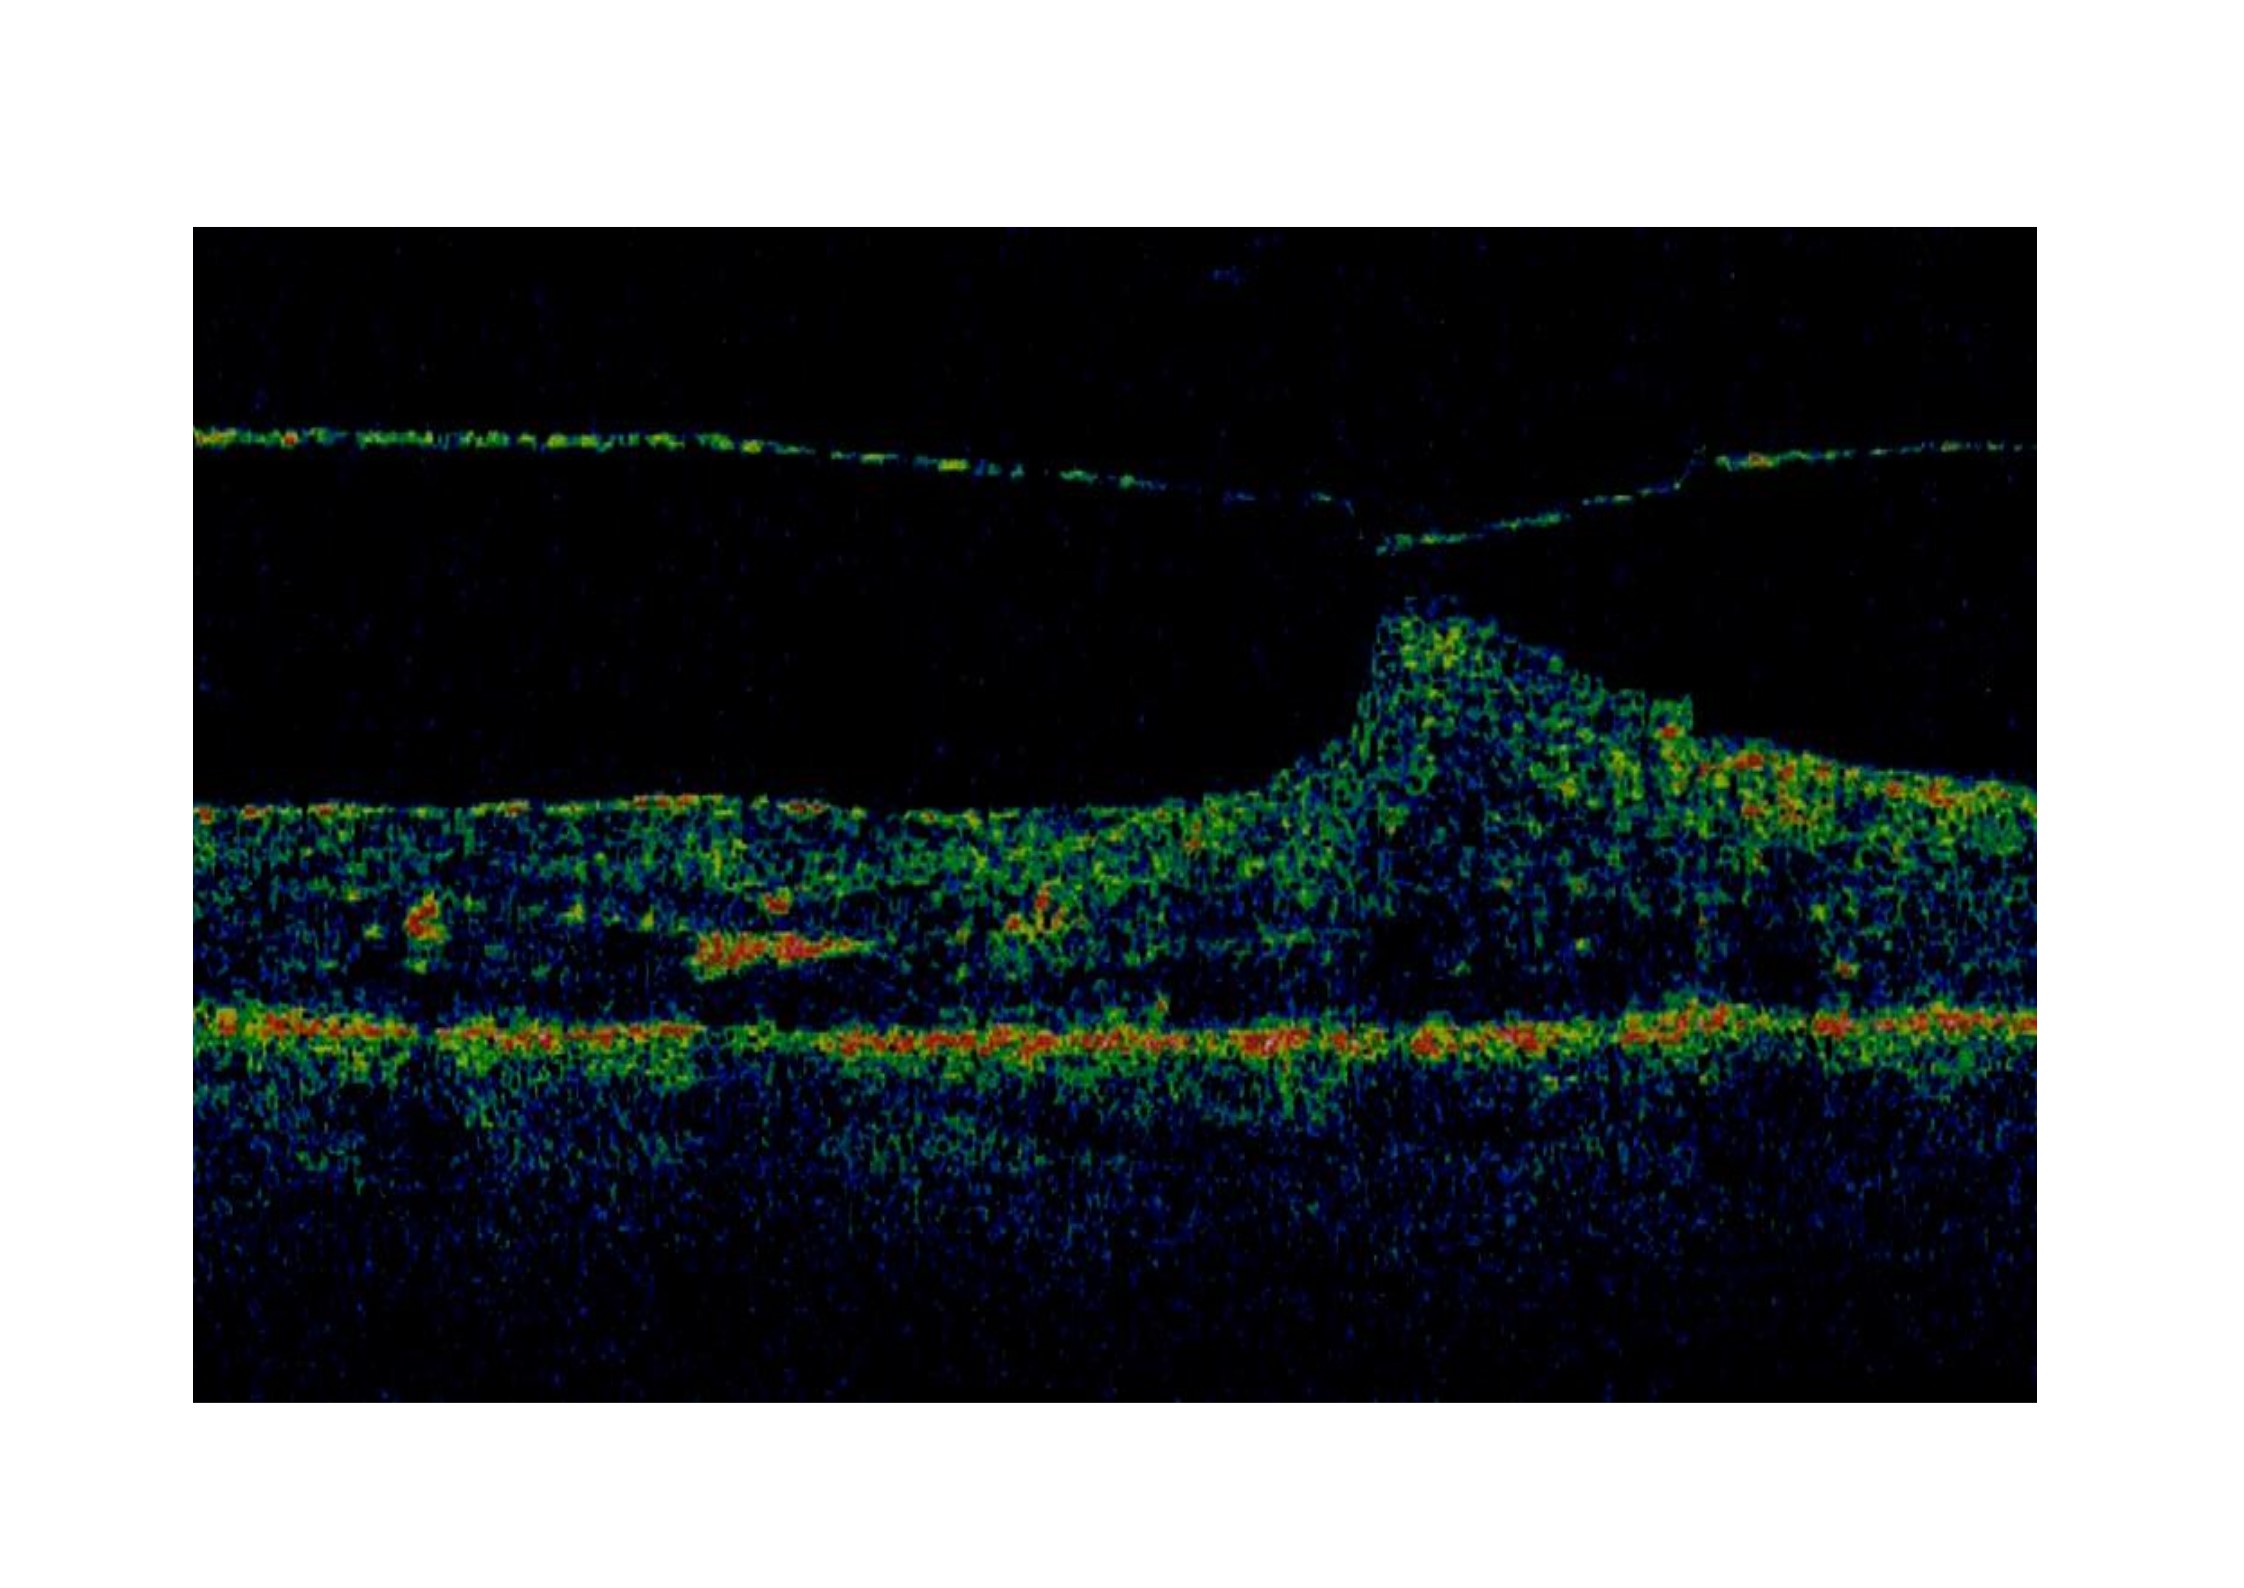

El síndrome de tracción vítreo-macular se caracteriza por un desprendimiento vítreo posterior incompleto o anómalo que provoca una tracción del vítreo residual sobre la mácula causando distorsión de la mácula y pérdida de visión, metamorfopsia, aniseiconia, visión borrosa o escotoma central. Muchas veces aocian membrana epirretiniana, edema macular cistoide o una hialoides posterior engrosada y tensa. En ocasiones puede traccionar de la retina hasta provocar un agujero macular completo.

Algunos casos, sobre todo cuando la arquitectura de la retina externa está preservada, son asintomáticos. Incluso, en un 11% de los casos, la tracción se resuelve espontáneamente, al despegarse el vítreo de la retina. Pero en muchos casos sintomáticos en que esto no ocurre puede ser necesaria la cirugía, es decir, una vitrectomía que permita despegar el vítreo y aliviar la tracción. Otras alternativas a las vitrectomía han sido la inyección intraocular de un gas (perfluoropropano), cuyos resultados se han publicado en una pequeña serie de casos no controlados (1) y más recientemente , en un estudio controlado con mayor número de pacientes, mediante el uso de ocriplasmina intravítrea, con resultados positivos (2).